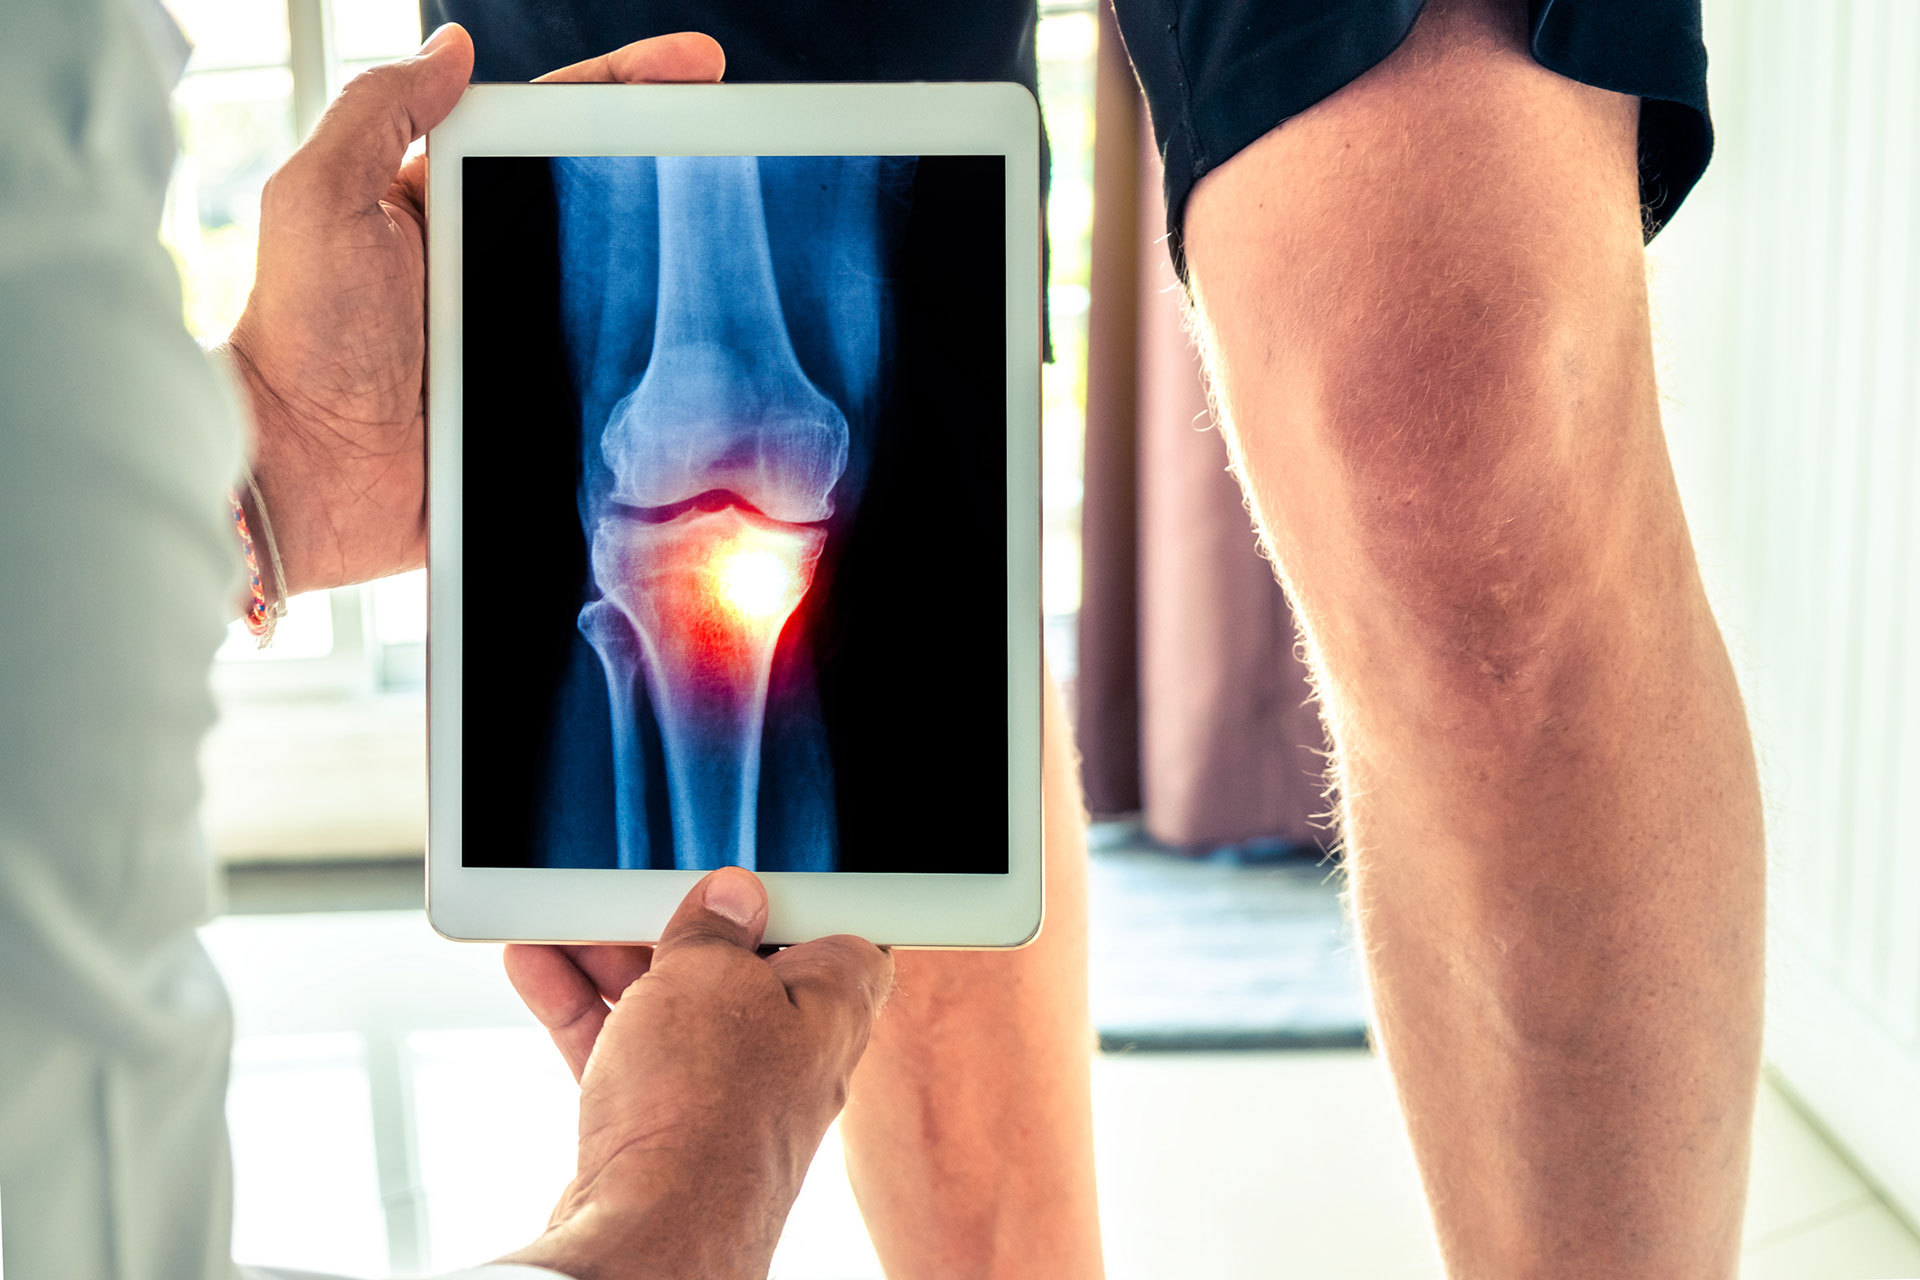

Other procedures using fluoroscopic guidance are evolving. Genicular nerve blocks that involve the usual 2 sets of diagnostic anesthetic blocks followed by blocks with RFA can be very helpful in patients with knee osteoarthritis that is either inoperable or has already failed knee joint replacement surgery. RFA nerve blocks to other joints such as the shoulder and hip for osteoarthritis are in development.